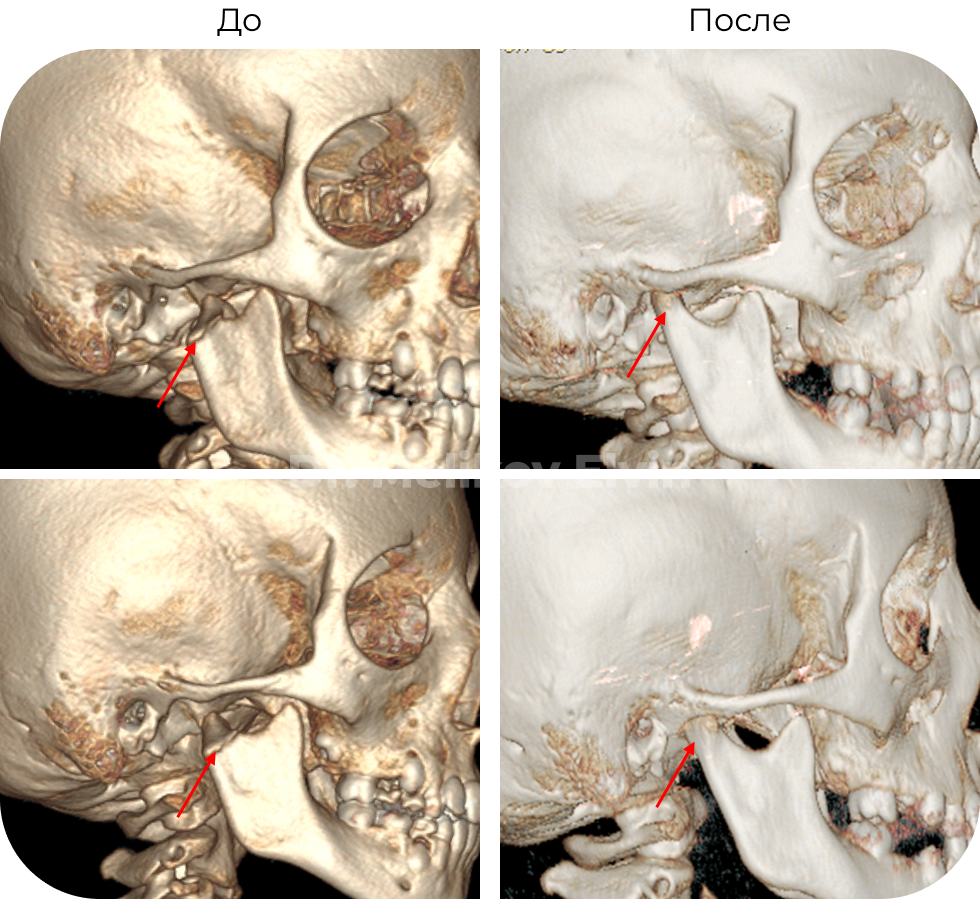

Безоперационное лечение перелома правого мыщелкового отростка нижней челюсти у ребенка 7 лет

🔹Диагноз: Перелом правого мыщелкового отростка нижней челюсти.

🔹Что получили: При дистракции правого внчс, под действием мышц, отросток репонировался и произошла полная консолидация.

До и после лечения

Обычно, в таких случаях, предлагают провести хирургическое вмешательство в объеме остеосинтеза мыщелкового отростка. Чтобы добраться к костным структурам, необходимо будет провести разрезы мягких тканей , в том числе и самой капсулы сустава. Не стоит так же забывать, что это ребёнок 7-8 лет, и при такой хирургии нарушаются зоны роста, что впоследствии может стать причиной асимметричный деформации челюстей, а еще хуже необратимых изменений в суставе. Протокол лечения таких детишек оставляет желать лучшего.

На кафедре Детской ЧЛХ Российского университета медицины изготовили специальную окклюзионную пластинку по индивидуальным параметрам, которая дала возможность провести дистракцию в суставе и безоперационно стать причиной реабилитации данного ребёнка. Результат на лицо!